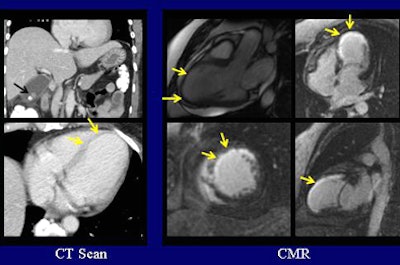

| In a 52-year-old man with right-upper-quadrant pain and leukocytosis, abdominal CT demonstrates gallstones (black arrow) and other findings suggestive of acute cholecystitis. Additionally, there is an area of anterior and apicoseptal wall thinning consistent with prior infarct. These regions also demonstrate delayed enhancement on postcontrast MR imaging. The cardiac findings were not discussed in the CT report. All images courtesy of Ashley Prosper and Jabi Shriki, MD. |